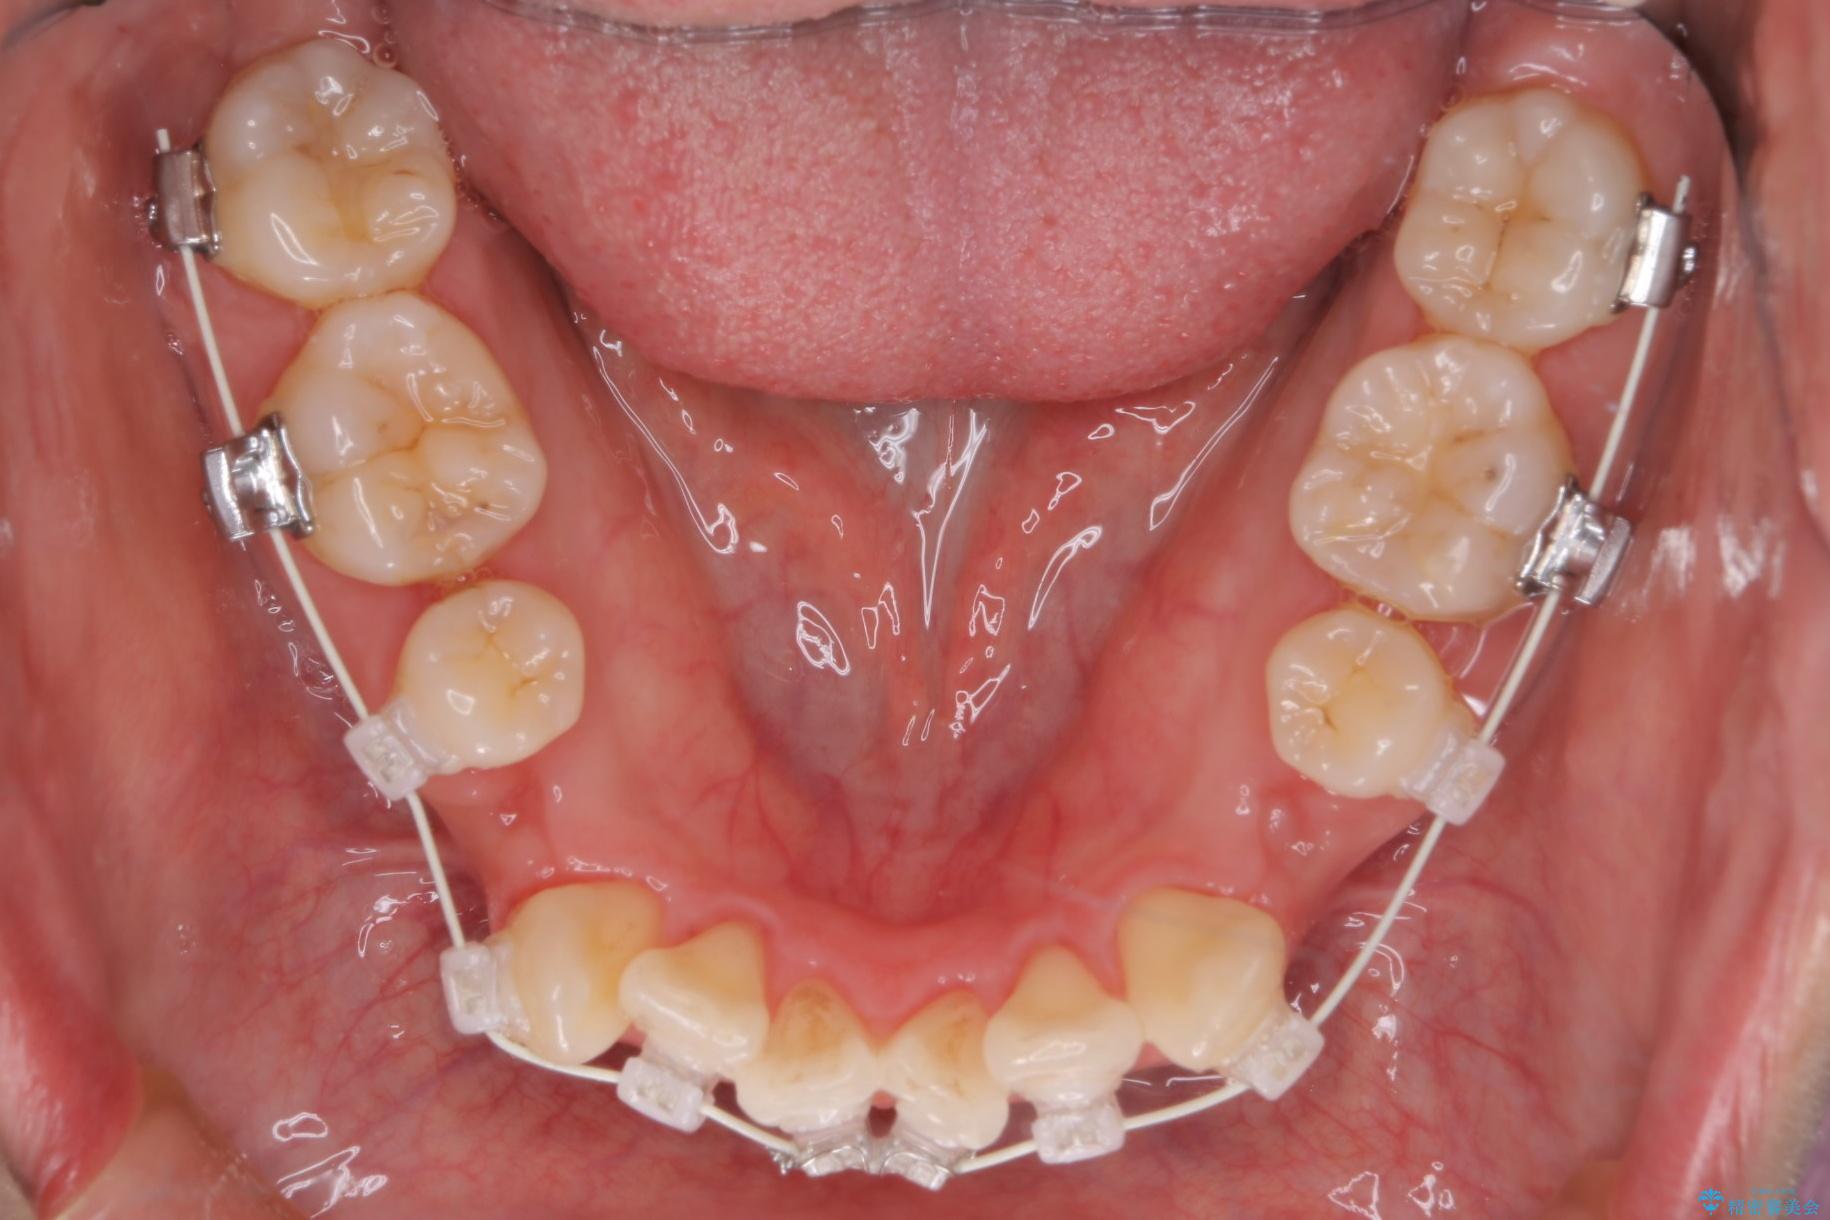

重度の叢生が認められたため、上下左右4番目の歯を抜歯しワイヤー矯正治療を行いました。

- 治療中は違和感や痛みが起こることがあります

- 症状により、抜歯が必要な場合があります

- 治療中は歯磨きがしにくくなるため、虫歯や歯周病になりやすくなります